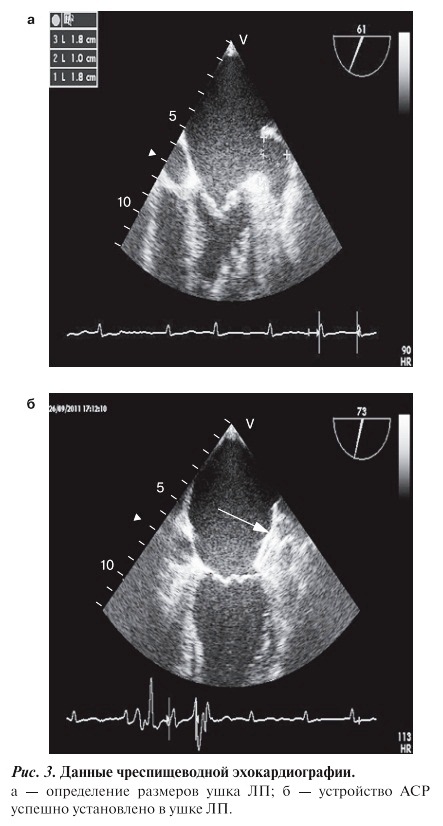

Устройства ACP нами впервые установлены осенью 2011 г. — 4 больным и в 2012 г. — 3. Таким образом, всем 7 больным устройство АCР успешно имплантировано. Все больные страдали постоянной формой МА неклапанной этиологии, в возрасте от 51 до 56 лет и имели противопоказания к антикоагулянтной терапии. Имплантацию устройства проводили под общей внутривенной анестезией на фоне искусственной вентиляции легких кислородно-воздушной смесью. Контроль за процедурой осуществляли с помощью флюороскопии с одновременным применением ЧП-ЭхоКГ. Для создания достаточной антикоагуляции во время процедуры рекомендовано введение гепарина с целью достижения активированного времени свертывания от 250—350 с. Ангиограммы УЛП до и после установки АСР представлены на рис. 2, данные ЧП-ЭхоКГ — на рис. 3.

Рис. 3. Данные чреспищеводной экокардиографии

На следующий день после процедуры всем больным была проведена трансторакальная ЭхоКГ, при которой были подтверждены правильное расположение АСР и отсутствие перикардиального выпота. В качестве антитромботической терапии больным был назначен прием ацетилсалициловой кислоты 100 мг/сут и клопидогрела 75 мг/сут на 45 дней. Отдаленные (через 12 мес) результаты первых 4 больных с АСР показали, что все они чувствовали себя хорошо, эпизодов тромбоэмболий и осложнений, обусловленных самим вмешательством, не было ни в одном случае.